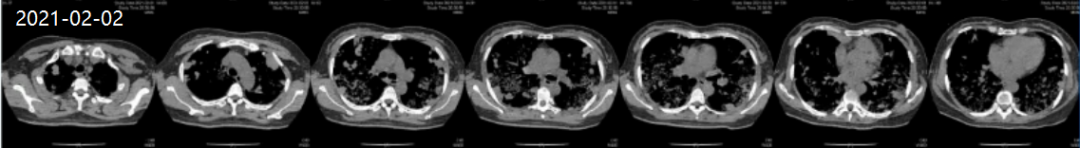

患者外院胸部CT(图1)和入本院当日胸部高分辨率CT(图2)均提示双肺多发团块影,肺泡积血表现,且进行性加重。

图2 患者胸部高分辨率CT检查结果(2021-02-02)